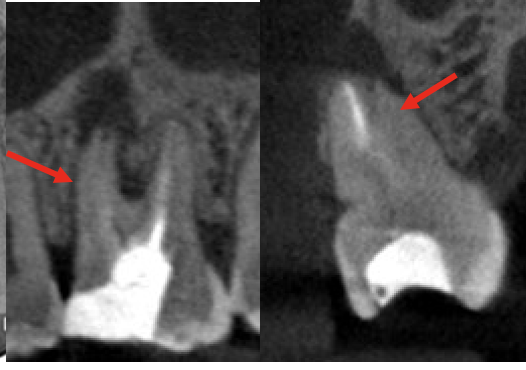

• 術前のCBCT画像、右上6の近心頬側根に大きな透過像(炎症の黒い影、赤矢印)があり、腫れの原因となっていることがわかる。未処置の根管、MB2(黄色矢印)は極度に石灰化していて根管のアウトラインも見られない。過去のラバーダム使用の自費の治療でもこういった部分が殺菌できないと病気を治すことは難しい。当院の再治療で石灰化根管の処置が可能かどうかは行ってみないとわからない、また上のケースのように殺菌ができても治らない場合もありえるため、より確実な方法として歯根端切除術を行うこととなりました。

• 術後1年の経過観察時のCBCT画像。治療前の炎症増は無くなり骨の再生が見られ経過良好です。石灰化MB2の部分に充填がなされていることがわかります(黄色矢印)。このように、感染除去を行って、しっかり封鎖をすることで根管治療を繰り返しても治らない難症例も治癒に導くことが可能です。